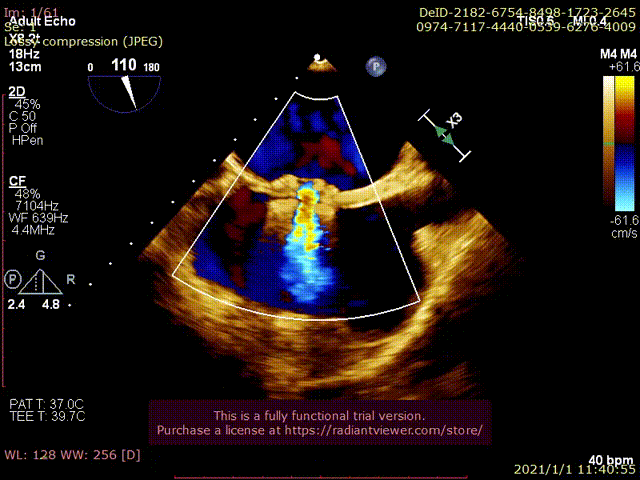

术中分流器形态稳定

食道超声可见左向右分流束